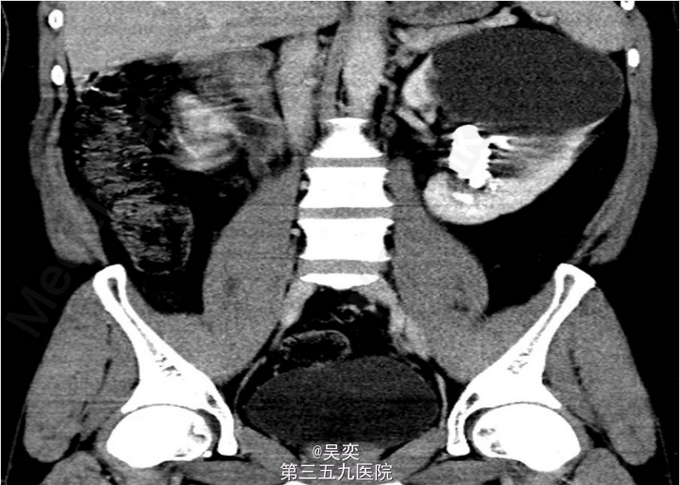

3、查体:无阳性体征 4、辅助检查:我院泌尿系B超:右输尿管上段结石并上段扩张,双肾多发结石。入院后白细胞总数10.550x10E9/L,中性粒细胞绝对值6.970x10E9/L。尿常规:白细胞计数50.30个/ul,红细胞计数145.70个/ul。生化全套:谷丙转氨酶75.000U/L,谷草转氨酶44.000U/L。双肾CTU:1、左肾盂和中下盏铸型结石较前稍增多,左肾中度积水。2、右肾多发结石,右肾中度积水,右侧输尿管上段炎症。3、左肾上极巨大囊性病变较前增大,考虑扩张的肾盏,内有结石。4、盆腔多发静脉石。5、前列腺小钙化灶。其余术前常规抽血结果无特殊。

5、诊断:肾积水伴输尿管结石,肾结石,精神分裂症 6、入院后完善相关检查,心电图、胸片未见异常,CT示:1、左肾盂和中下盏铸型结石较前稍增多,左肾中度积水。2、右肾多发结石,右肾中度积水,右侧输尿管上段炎症。3、左肾上极巨大囊性病变较前增大,考虑扩张的肾盏,内有结石,排除手术禁忌症,经术前准备,于左侧经皮肾镜碎石取石术,手术顺利,术后恢复较好。